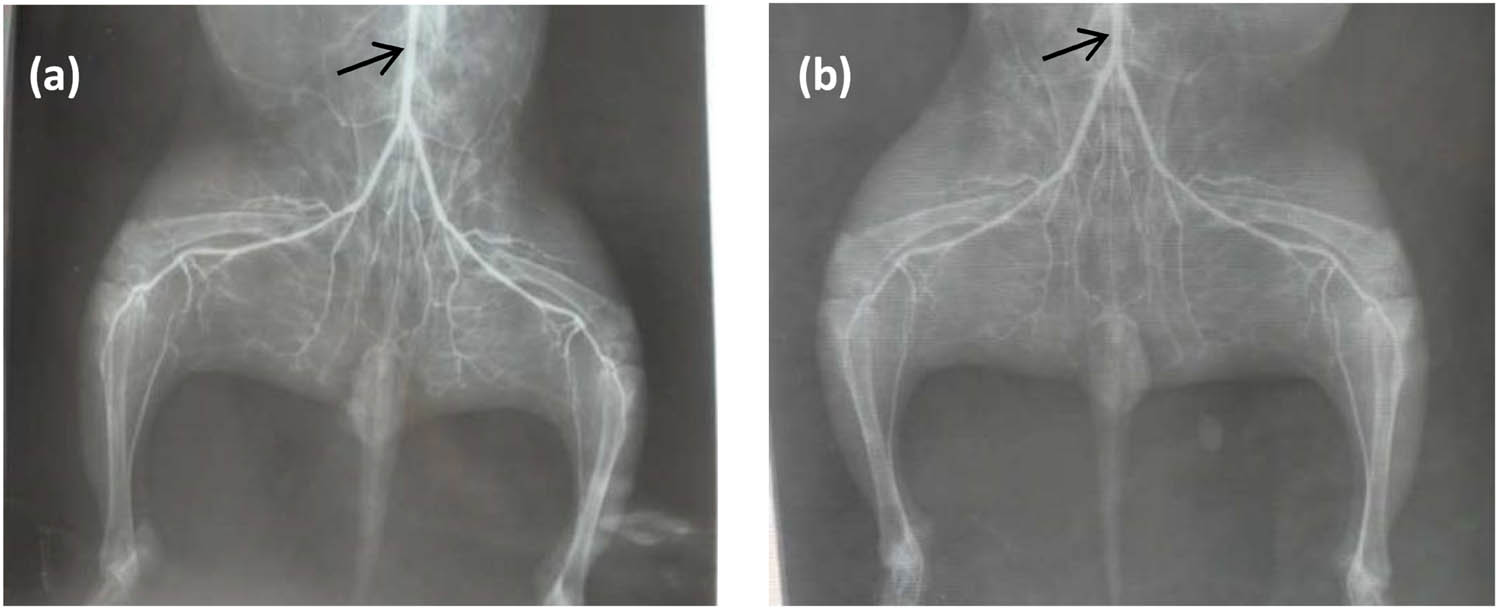

Figure 4 shows the strut located at the vascular branch position with a degradable iron stent after 9 months of implantation. As shown, the surface of the strut is relatively smooth, and also no obvious corrosion product was found. To evaluate the risk of thrombosis brought by the stent malposition, the rabbits’ lower limbs vessels’ X-ray morphology was performed before the rabbit was sacrificed at 3 and 9 months separately (Figure 5). As seen, there were no obstacles found and there was no abnormal blood flow of the downstream vessels.

Rabbits’ downstream vessels’ X-ray morphology with a degradable iron stent at the iliac artery position: (a) 3 months after implantation; (b) 9 months after implantation, arrow position stand for the position of the implanted stent.